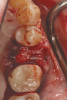

Figure 7 demonstrates the handling of the material as it is inserted into a large, mandibular molar extraction socket. The graft was covered with a collagen barrier, but no primary closure was either planned or obtained. The area healed uneventfully and was reentered with a flap procedure at 8 months for implant placement (Figure 8). Based on Figure 8 it is evident that much of the graft material had resorbed and was replaced with vital bone while the width of the alveolar ridge was preserved to facilitate ideal placement of an endosseous dental implant.

Fig 7. Insertion of the PLGA-TCP self-setting composite graft material in the extraction socket.

Figure 7

Fig 8. Eight months after grafting the extraction socket an implant was placed in a well-healed ridge. (Surgery in this case performed by Dr. Leventis.)

Figure 8